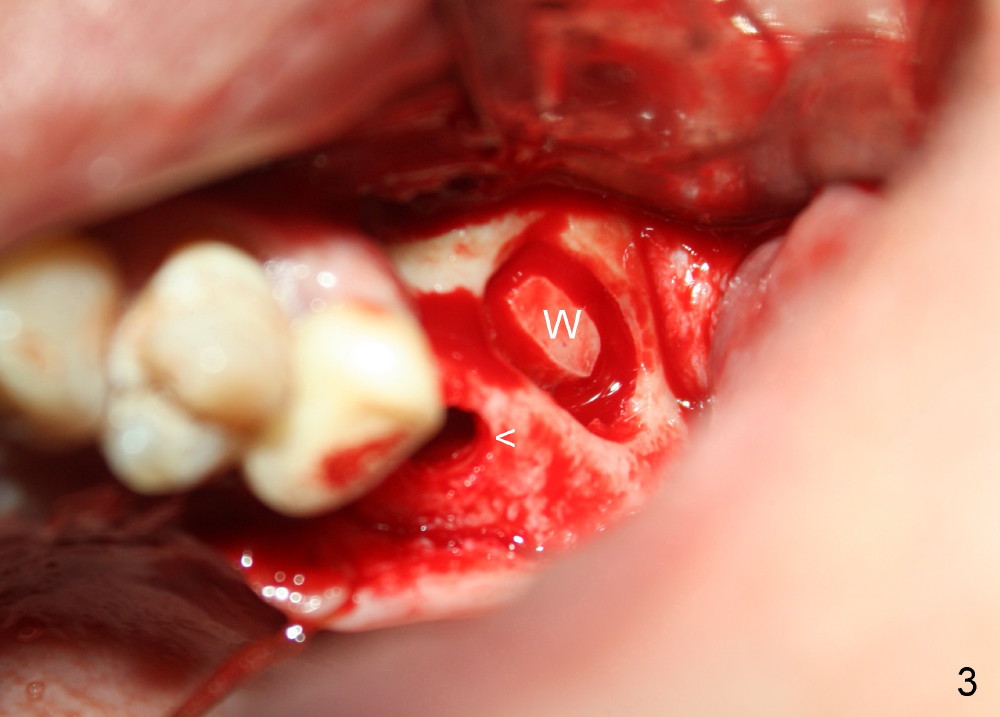

A lateral sinus window is created with a round diamond bur in high speed handpiece with copious irrigation as planned (Fig.3 W). The sinus membrane is lifted without tear. With the membrane protected with 2x2 gauze, an osteotomy (Fig.3 <) is developed at the site of the tooth #14 with 2 mm pilot drill, 2.5-3.5 mm reamers, 5x11 mm tap (Fig.1: T) and 6x11 mm tap. A synthetic bone graft (Osteogen 300-400 micron) is placed in the sinus before placement of 6x11 mm implant (Fig.4: 14). More of the synthetic bone mixed with autogenous bone is added superficial to the apex of the implant inside the sinus. The flaps are sutured.